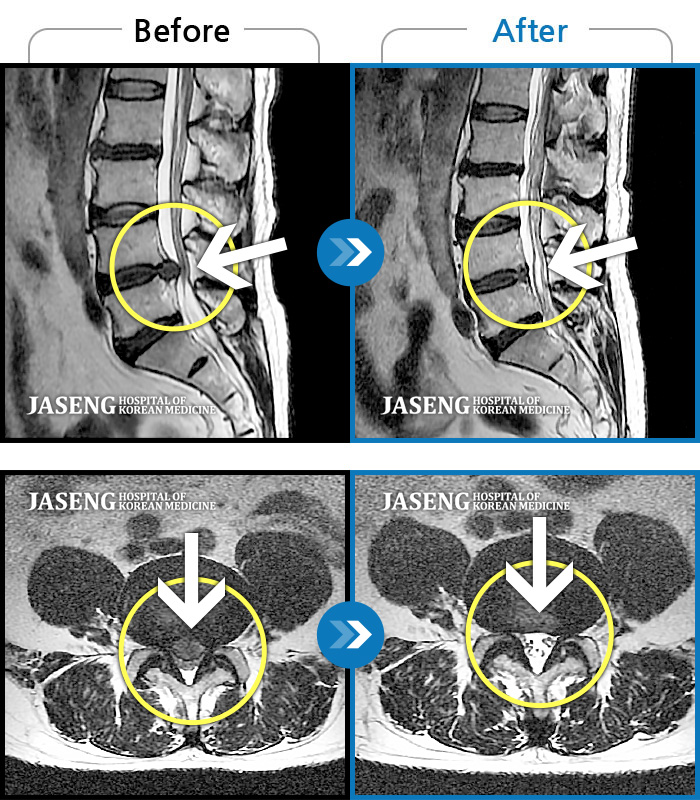

제가 가지고 간 MRI 영상자료를 보시면서 수술하지 않고도 충분히 고칠수 있다는 희망적인 말과 증상에 대해 자세히 설명해주시고 앞으로 어떻게 치료할 것인지에 대하여 알기쉽게 설명해주셔서 감사했습니다.